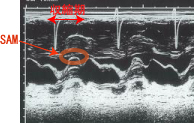

<心エコー>

・ASH(アッシュ;asymmetric septal hypertrophy;非対称性中隔 肥大):肥大型心筋症では、右心室と左心室の間にある心筋(中隔)が外側の心室の壁に比べて 異常に太くなります。

・SAM(収縮期の僧帽弁前尖の前方運動):HOCMでみられます。

・大動脈弁半分閉鎖:HOCMでは収縮中期に駆出される血液量低下のために大動脈弁が閉じかかる所見を 呈します。したがって、頚動脈波では二峰性脈が見られます。

HOCM(心エコー) (97回医師国家試験D20)